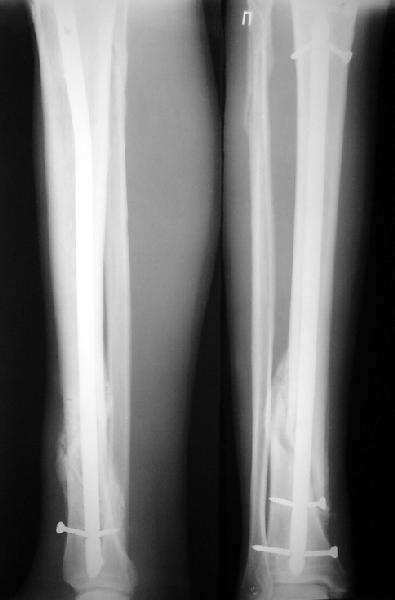

Ok. А также и следующий, в 3 месяца.

Это наглядная демонстрация возможности ранней полной нагрузки при нестабильном по оси повреждении, причем не в самых благоприятных механических условиях - при плохом сопоставлении, со слабым фиксатором.

Покажите, пожалуйста, другие примеры подобных переломов, оперированные с более толстыми запирательными шурупами и дающими полную нагрузку в первый месяц после остеосинтеза.